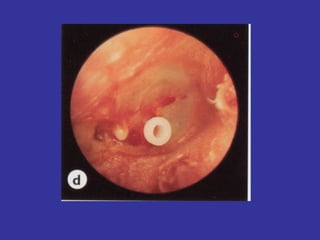

Timpanostomy Tubes:   Insertion of ventilation tubes in the TM for ventilation/drainage. (Silicone) most recent development  Incision on Anterior Inferior region. Not responding to ATB treatment Recurrent AOM infections in a period of time *Uni or bilateral chronic OME  for more than 3 months. *Conductive hearing loss in excess of 30 dB in patients with  Otitis media with Effusion  *Recurrent AOM infections: Children with > 3 separate episodes within 3 months Children with  4 episodes in a 6 months period or  with  6 episodes in a 12 months period

AOM WITH OTORRHEA THROUGH TYMPANOSTOMY Insertion of ventilation tubes in the TM for ventilation/drainage. Otorrhea is a major complication after their insertion Bacterial isolated:  S.pneumonia, H. influenza, M. catarrhalis,  S.aureus, P. aeruginosa. S/S:  Fever, draining from ear, earache. Tx:  Due to the inflammatory response from these bacterias, it is  better to combine an Atb with  dexamethasone 0.1% topical. (Ciprodex Otic for patients above 6 months, Floxin) If it is necessary, can give oral Atb.

AOM WITH OTORRHEATHROUGH TYMPANOSTOMY Insertion of ventilation tubes in the TM for ventilation/drainage. Otorrhea is a major complication after their insertion Bacterial isolated: S.pneumonia, H. influenza, M. catarrhalis, S.aureus, P. aeruginosa. S/S: Fever, draining from ear, earache. Tx: Due to the inflammatory response from these bacterias, it is better to combine an Atb with dexamethasone 0.1% topical. (Ciprodex Otic for patients above 6 months, Floxin) If it is necessary, can give oral Atb.